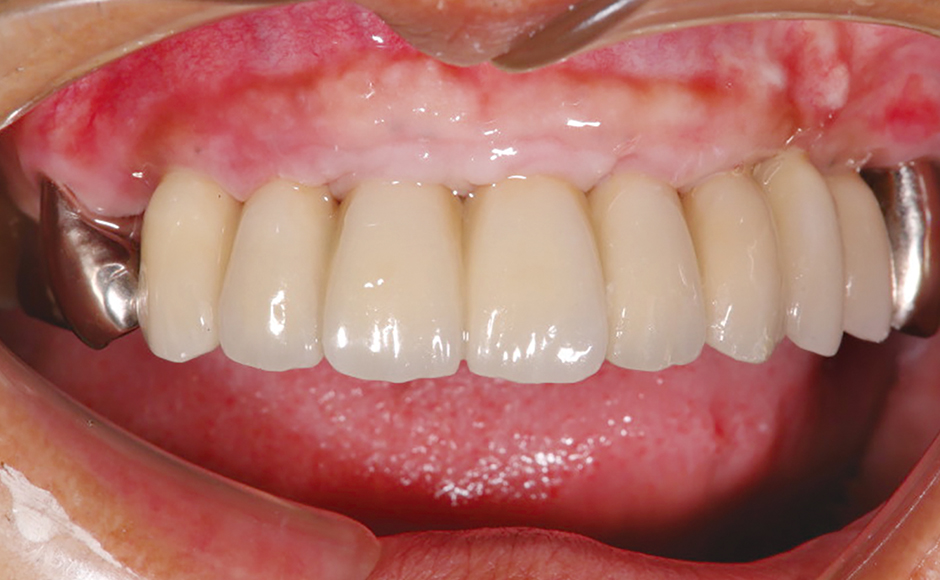

症例1:患者の主訴を考慮し、抜歯即時埋入・即時プロビジョナライゼーションを計画